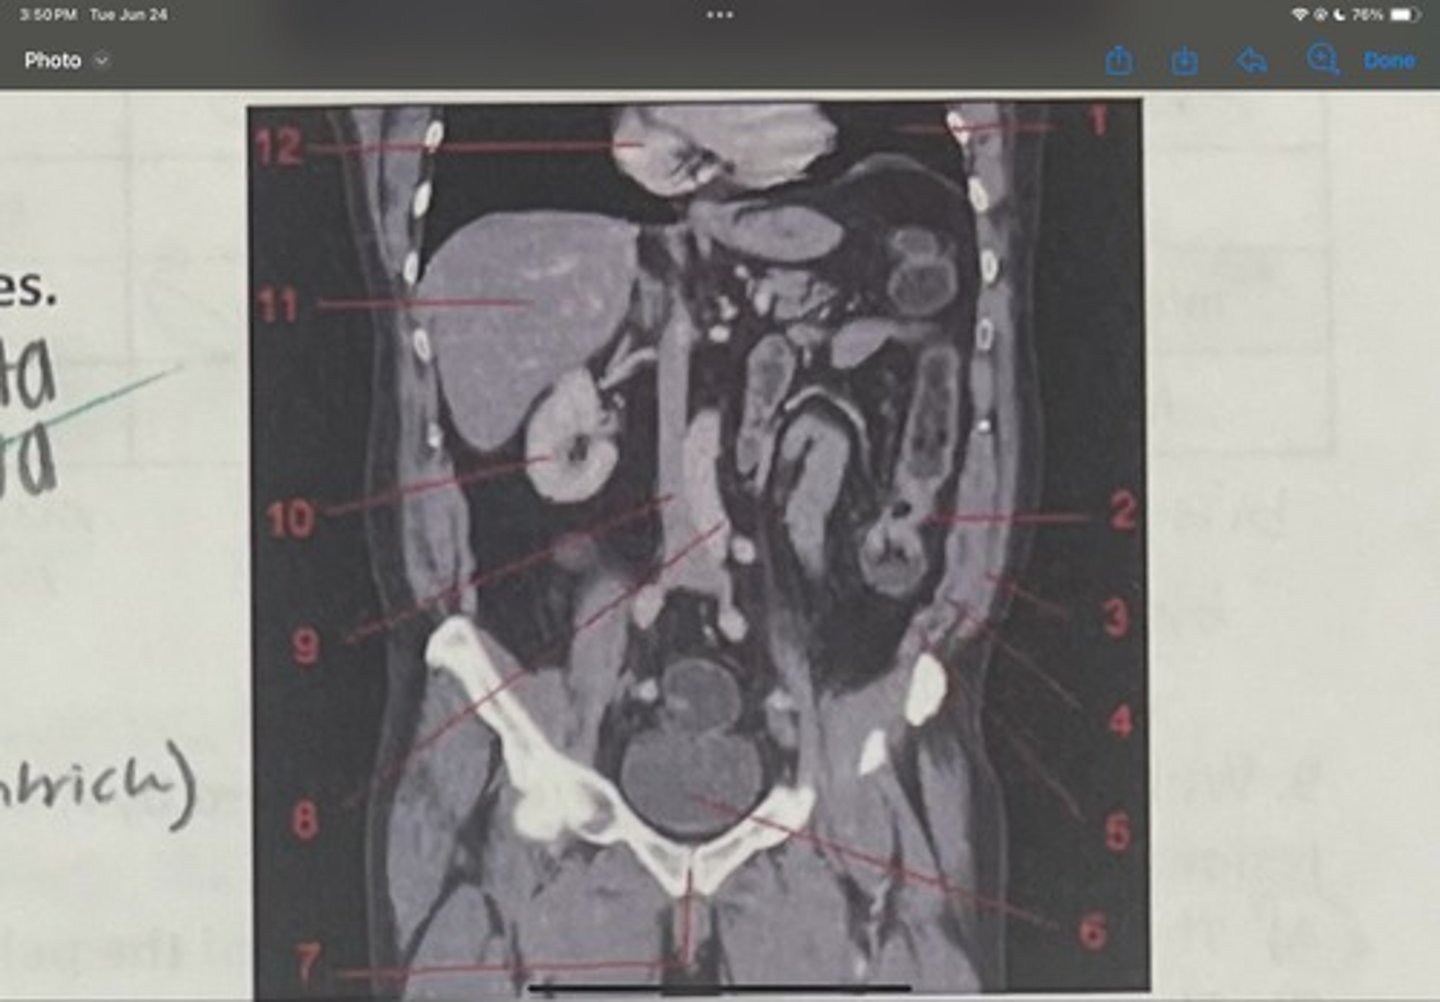

What is 1

Descending colon

What is 2

External oblique

What is 3

Internal obliques

What is 4

Transversus abdominis

What is 5

Bladder

What is 6

Pubic sysmphysis

What is 7

Abdominal aorta

What is 8

Inferior vena cava

What is 9

Right kidney

What is 10

Liver

What is 11

Heart (right ventricle)

What is 12

Subcostal nerve (T12)